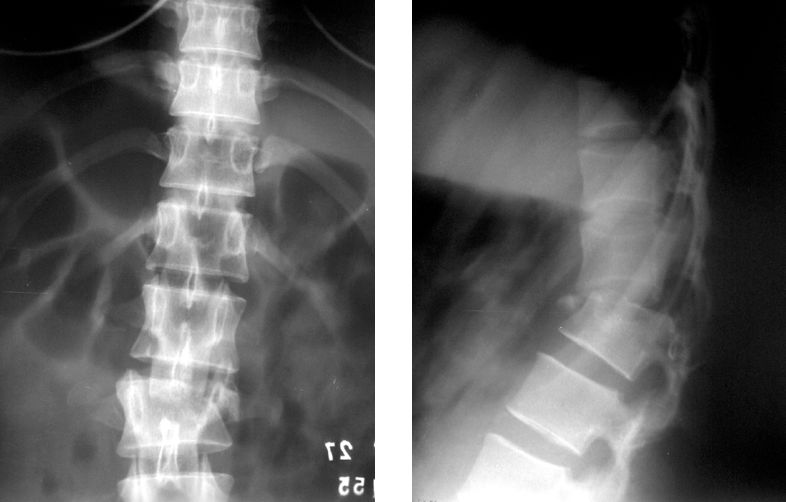

Si tout le corps est stable, la fracture déplacée doit être opérée immédiatement en cas de symptômes neurologiques.